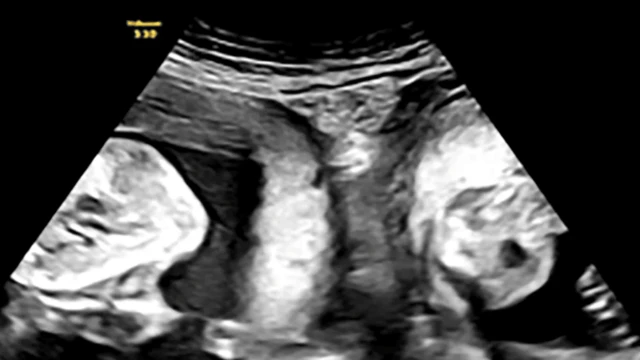

Mwanamke aliye na hali ya nadra ya mifuko miwili ya uzazi amejifungua mapacha, mtoto mmoja kutoka kila mfuko, mwezi uliopita katika hospitali moja kaskazini magharibi mwa China, kulingana na maafisa wa afya na vyombo vya habari vya serikali.

Mama huyo, ambaye jina lake la mwisho ni Li, alimkaribisha mvulana na msichana kwa njia ya upasuaji katika Hospitali ya Xi'an katika mkoa wa Shaanxi, walisema maafisa, na kuliita tukio "moja kati ya milioni."

Kwa mujibu wa hospitali hiyo, mama huyo aliyejifungua alizaliwa akiwa na mifuko miwili ya uzazi, hali inayopatikana kwa mwanamke 1 kati ya 2,000.

Mwezi Januari, Li alipata ujauzito na ndipo ikagundulika kupitia vipimo kwamba alikuwa anatarajia watoto wawili - na kila mmoja katika mfuko wake.

Baada ya ufuatiliaji wa "karibu wa matibabu, "alifanikiwa" kujifungua mvulana mwenye uzito wa kilogramu 3, na msichana mwenye uzito wa kilogramu 2, hospitali ilisema.